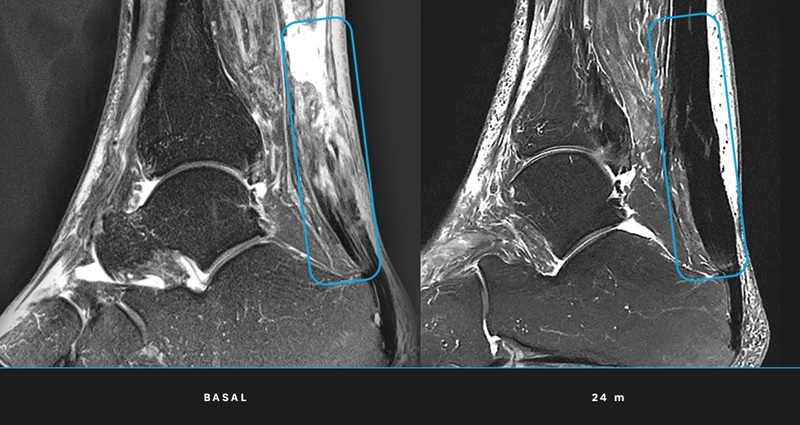

- Regeneración total: Las resonancias magnéticas confirmaron que todos los pacientes alcanzaron la regeneración completa del tendón al término del seguimiento de 24 meses.